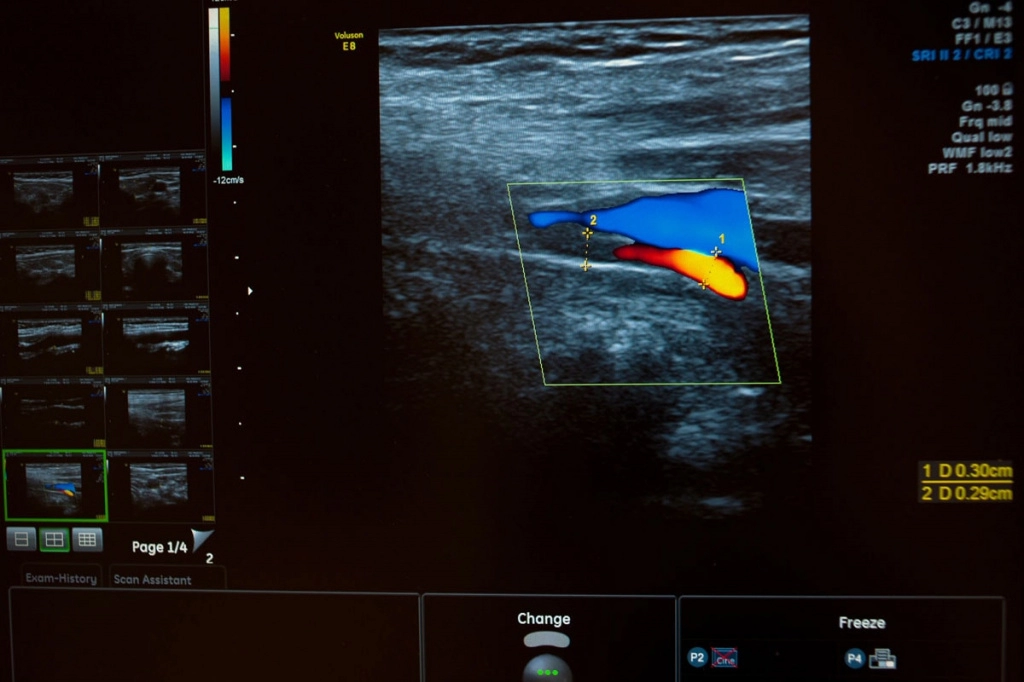

Не просто ультразвуковая диагностика

АО «Медицина» (клиника академика Ройтберга), помимо стандартных исследований, предлагает своим пациентам допплерографические исследования сосудов и ЗD/4D УЗИ.

Допплерографическое исследование позволяет определить:

• скорость кровотока в сосудах;

• направление кровотока;

• ширина просвета в сосудах;

• давление в сосуде.